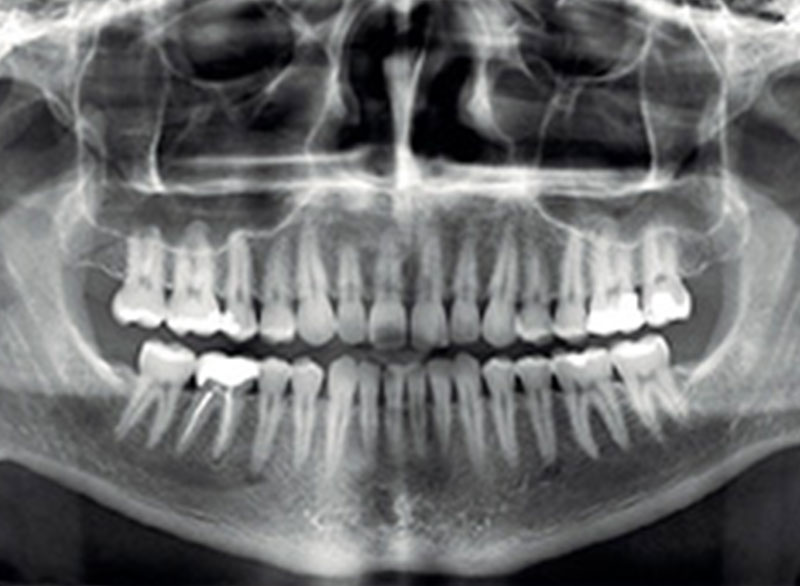

A panoramic x-ray machine that we use to take images of your whole mouth to see the teeth.